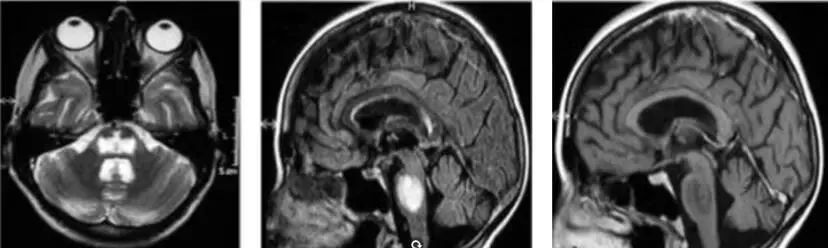

慢性低钠血症患者的治疗与渗透性脱髓鞘综合征(脑桥中央髓鞘溶解症)的发生相关。通常血清钠水平纠正后的2~6天会出现构音障碍、吞咽困难、惊厥、意识状态改变、四肢轻瘫及低血压等症状?;颊吆喜⒌图匮?、饮酒史、肝移植及女性患者更倾向于出现这种不可逆的状况。

治疗:支持、对症治疗为主。甘露醇、速尿、大剂量激素冲击治疗、高压氧、血浆置换治疗。

图1 渗透性脱髓鞘综合征脑部病变